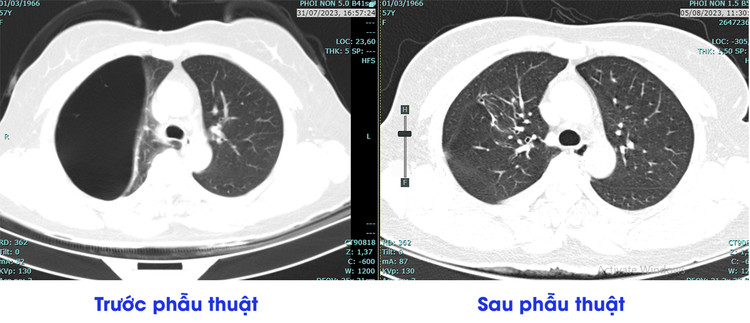

Hình ảnh chụp CT của người bệnh kén khí phổi trước và sau phẫu thuật |

Tại Bệnh viện đa khoa tỉnh Phú Thọ, sau khi được bác sĩ thăm khám, thực hiện các chỉ định chụp chiếu, cho hình ảnh kén khí phổi khổng lồ trong phổi người bệnh (kén khí kích thước khoảng 13x7cm).

Sau phẫu thuật 3 ngày người ổn định, phục hồi tốt, ít đau vết mổ, phổi giãn nở tốt, bệnh nhân có thể vận động nhẹ nhàng, đi lại bình thường.